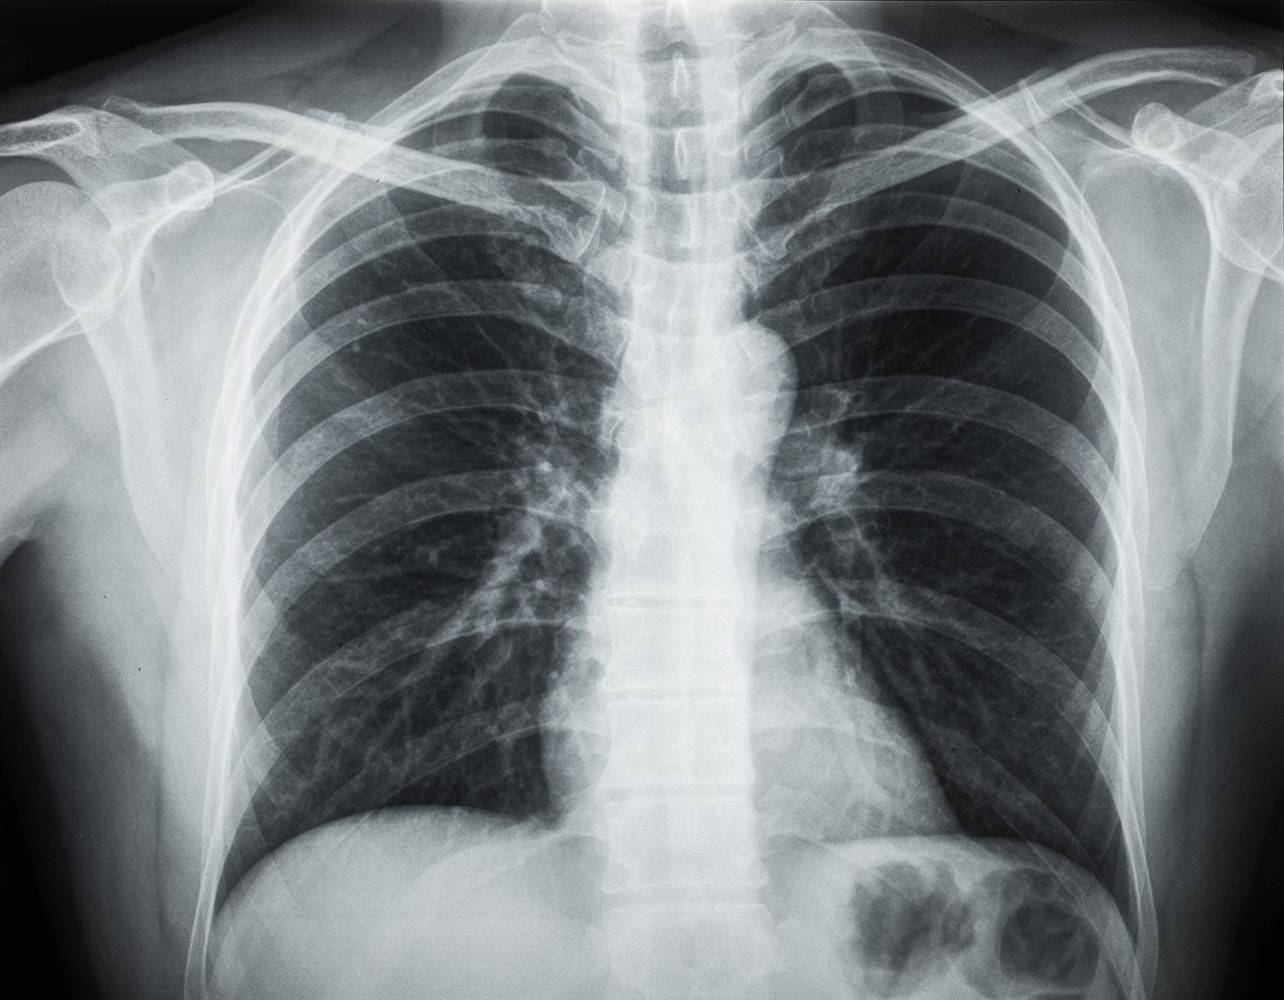

V Zasebni ambulanti za pljučne bolezni opravljamo preglede in diagnostiko pljučnih bolezni (rentgenske preiskave pljuč in srca, spirometrijo, alergološka in metaholinska testiranja) ter zdravljanje pljučnih bolezni.